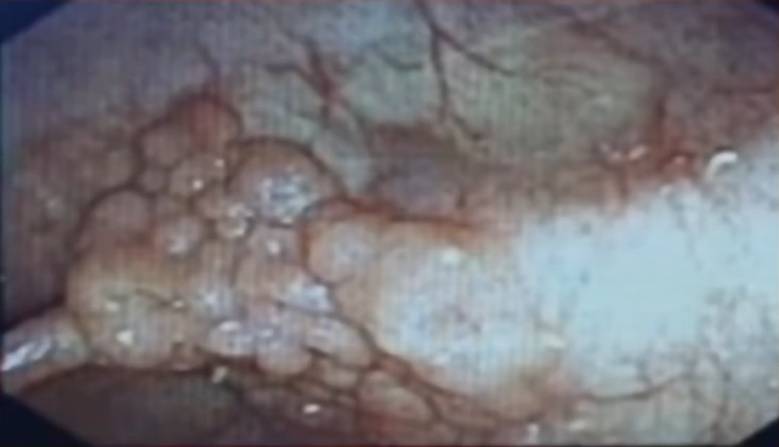

很多人在做肠镜的过程中会被医生告知肠道内出现息肉,但不是所有的息肉都和肿瘤相关。息肉可分为腺瘤样息肉和炎性息肉,其中腺瘤样息肉是有可能发生癌变的。

腺瘤样息肉有不同的形态,包括无蒂型肠息肉、侧方生长型肠息肉、有蒂型肠息肉以及亚蒂型的肠息肉,它们都有最终发生癌变的风险。

但是其中基地宽大,和肠壁结合面大的腺瘤样息肉癌变风险要大于带蒂的息肉,更需及时治疗。

专家告诉我们,一般认为从一个腺瘤样的息肉发展成肠癌需要10多年的时间,所以发现了自己有腺瘤样的息肉时应尽早手术切除,以免造成为更严重的后果。